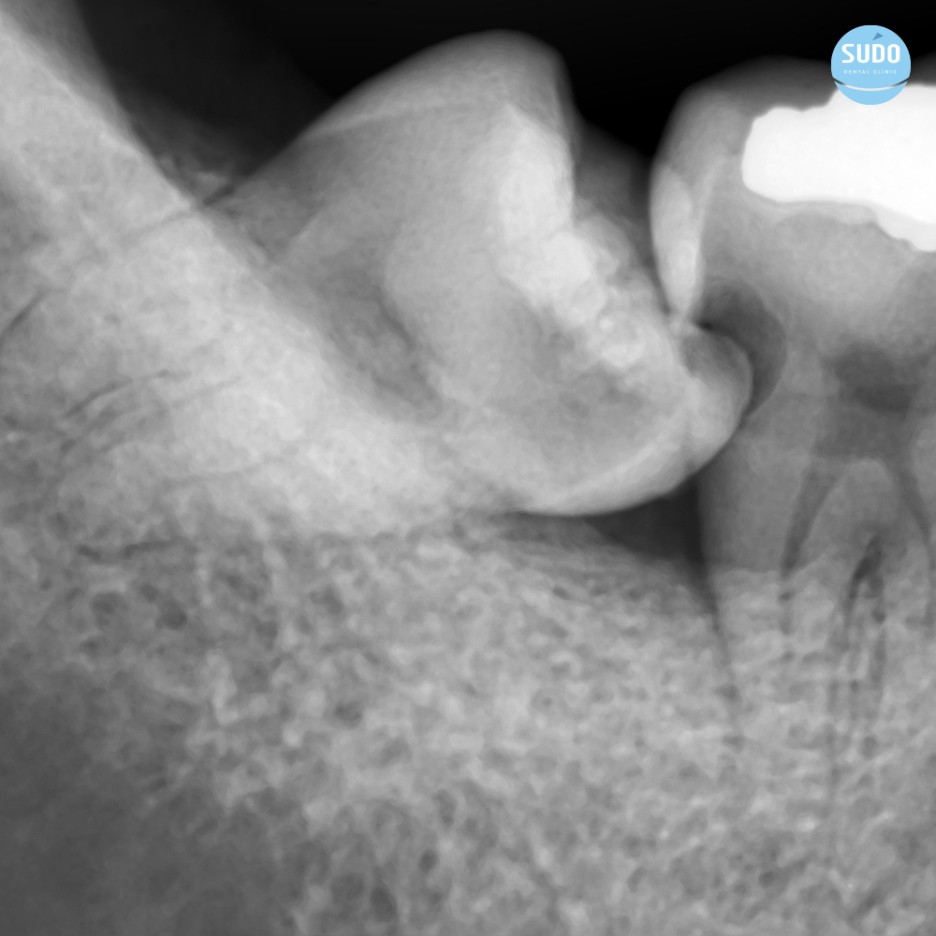

위 환자분은 파노라마 X-ray를 확인한 결과, 비스듬하게 누워있는 ‘부분 매복 사랑니’에 충치가 관찰되었습니다.

앞어금니에까지 신경을 침범한 ‘치아 사이 충치’ 또한 보이는데요, 매복 사랑니와 어금니 사이에 계속해서 이물질이 끼여 이가 썩은 것으로 사랑니 충치와 사랑 니로 인한 어금니 충치를 치료하기로 계획하였습니다.